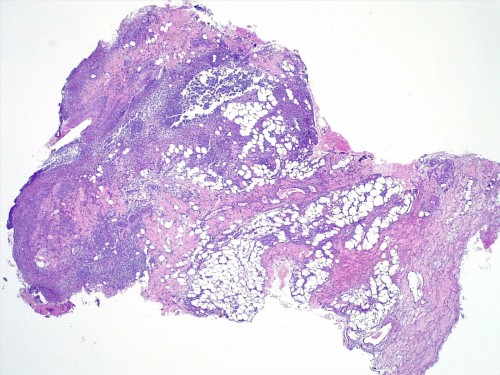

– les biopsies cutanées (LAPVSO) concluent à de sévères lésions de dermohypodermite neutrophilique avec furonculose et lésions hypodermiques ponctuelles de vascularite leucocytoclasique (Photos 4 à 9)

Examen histopathologique montrant un épiderme intact ou sévèrement ulcéré. Dans le derme, on observe un œdème superficiel ainsi que de multiples foyers inflammatoires non encapsulés, souvent à point de départ folliculaire ou périfolliculaire, pouvant fusionner, rompre les follicules pileux et s’étendre dans l’ensemble du derme voire gagner l’hypoderme. Ces foyers sont caractérisés par l’accumulation de granulocytes neutrophiles qui semblent altérés et qui dissèquent les fibres de collagène autour du follicule pileux ainsi que la paroi folliculaire et la lumière folliculaire. De nombreuses plages inflammatoires contiennent des tiges pilaires nues. L’infiltrat peut s’étendre dans l’hypoderme, mais ce dernier est surtout caractérisé par un épaississement des septa conjonctifs interlobulaires du tissu adipeux avec œdème, accumulation d’un matériel fibrinoïde, dilatation vasculaires des vaisseaux lymphatiques et des structures vasculaires de petit calibre, les vaisseaux lymphatiques étant encombrés d’un matériel inflammatoire fibrino-leucocytaire. Il peut exister des images focales de vascularite leucocytoclasique au sein de l’hypoderme.